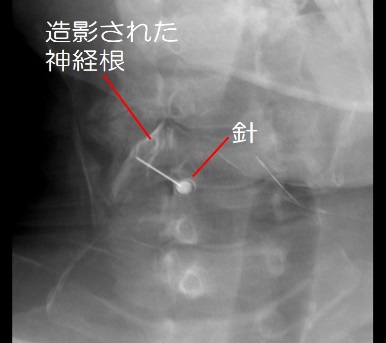

障害されている神経根を同定するために針をついて麻酔薬を注入する神経根ブロックを行うことがあります。